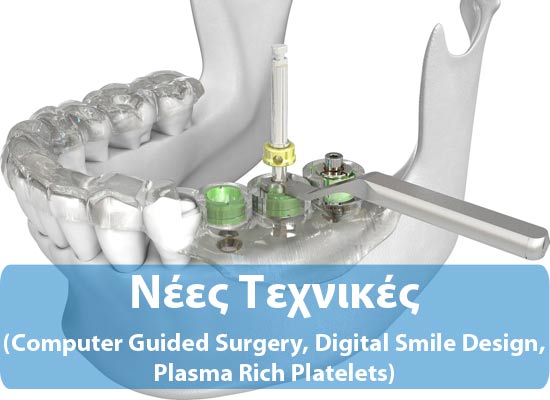

ΝΕΕΣ ΤΕΧΝΙΚΕΣ - COMPUTER GUIDED SYRGERY (DSD, PRP)

Στην εποχή των ραγδαίων εξελίξεων όσον αφορά χειρουργικές τεχνικές και υλικά, θεωρείται πλέον δεδομένο ότι τα οδοντικά εμφυτεύματα ,που αντικαθιστούν τη ρίζα του φυσικο...